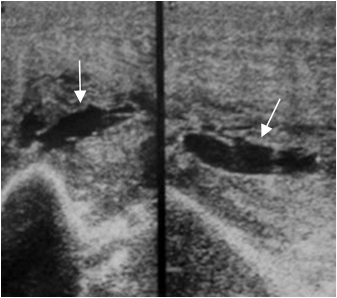

Fig 38 B. Ruptura del biceps.

Ecografía. Pérdida del patrón fibrilar en el biceps, ruptura de algunas fibras y colección en la parte inferior, por lesión muscular tipo 2.